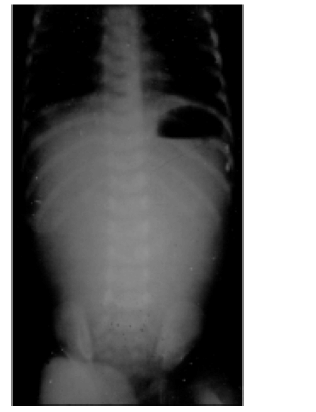

Considerando a imagem apresentada, da radiografia do abdome em incidência anteroposterior de um lactente com ausência de conteúdo gasoso em intestino delgado e intestino grosso, além de ectasia gástrica com considerável nível hidroaéreo, é correto presumir que o diagnóstico da seguinte malformação gastrintestinal é